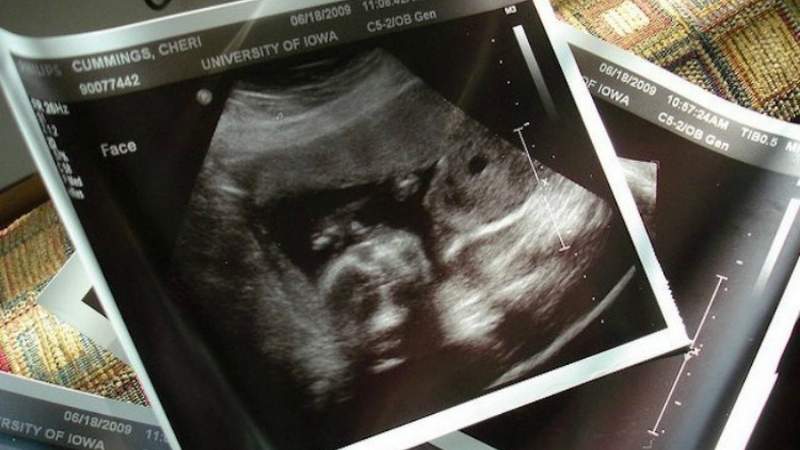

Por otro lado, la señora jamás se hizo ni una ecografía, y eso que los médicos se lo habían pedido.